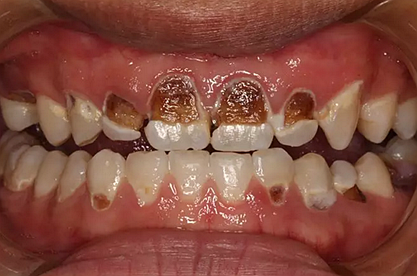

我們的主人今年才25歲,可卻從很小的時候就嗜好喝可樂等碳酸飲料,幾年下來,讓我們兄弟姐妹們整天浸在碳酸里受這蝕骨之痛,原本皎潔的外貌如今早己經(jīng)是腐蝕不堪、丑陋無比,更有甚者,一些兄弟姐妹們已經(jīng)病入膏肓,被病痛折磨奄奄一息。

下面是醫(yī)生眼中和ct下的我們

一身病痛啊

牙結(jié)石、牙齦炎癥、牙體殘缺、慢性牙髓炎、蛀牙......